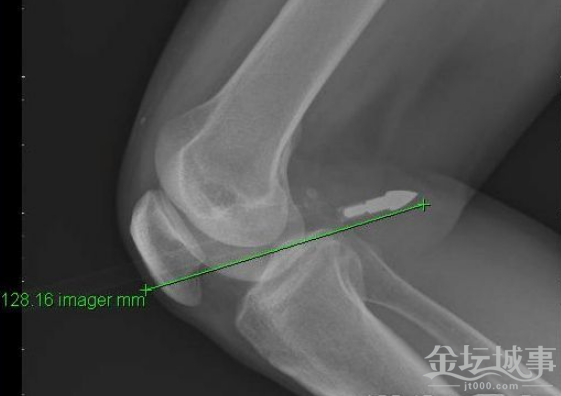

箭头射进膝盖内,留在外面的箭身足有70—80CM长。

长沙1月19日讯 都说暗箭难防,家住长沙井湾子51岁的王琛华(化名)可算是体会这句话了,他在晾衣服时被一只飞来的利箭射伤了膝盖,金属箭头穿透膝盖足有12CM,被家人紧急送往长沙市中心医院抢救。1月19日,记者从长沙市中心医院获悉,经紧急手术才及时将箭头取出,目前王先生正在留院观察中。